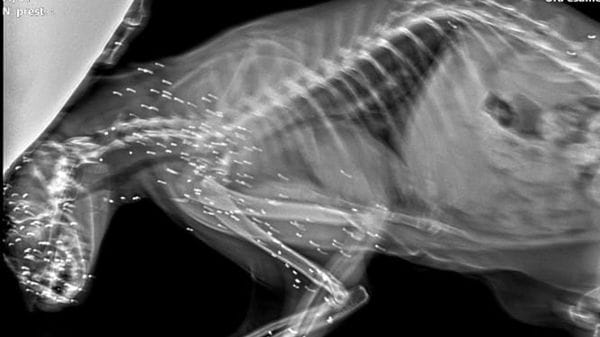

È stato iscritto nel registro degli indagati un 46enne residente a Trivigno per la morte di Lucia Tognela, 59 anni, trovata senza vita lungo un sentiero a Tirano. L’ipotesi è di omicidio colposo nell’ambito di un’indagine che ruota attorno a cinque cani sequestrati all’uomo. Decisivi saranno l’autopsia e gli accertamenti tecnici per chiarire le cause del decesso